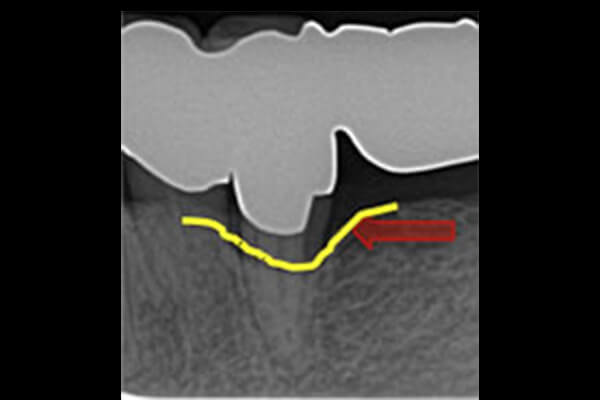

症例 症例

再生療法を行なった部位の術前と術後のレントゲンになります。矢印のところで骨の再生が確認できます。